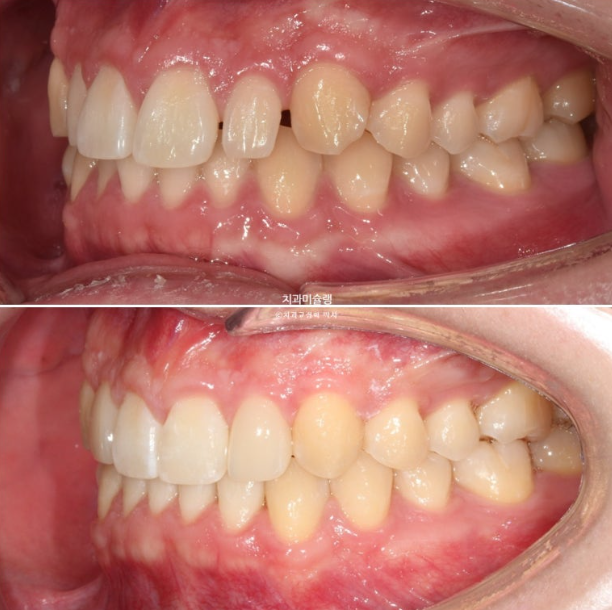

중심선 등을 좀 더 바로잡고자 재제작에 들어갑니다.

재제작 장치는 17개가 나왔고 24년 5월부터 24년 11월까지 꼈습니다.

24.11

위 아래 중심선은 정확히 맞고

어금니 교합관계도 1급 입니다.

모든게 좋지만 환자분의 요구사항도 있었고 완성도를 위해 재제작을 1회 더했습니다.

11개 추가장치를 모두 낀 후 25년 6월 치료를 마무리 합니다.

이제 왜소치 무삭제 라미네이트가 들어갈 차례 입니다.

어금니 교합은 좋고 1급 교합관계를 보입니다.